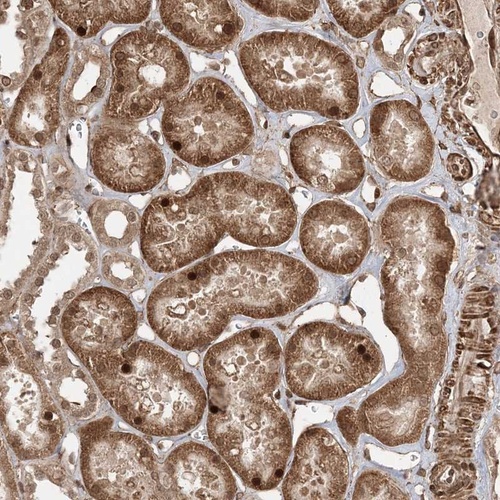

Immunohistochemical staining of human kidney shows distinct nuclear and cytoplasmic positivity in tubular cells.